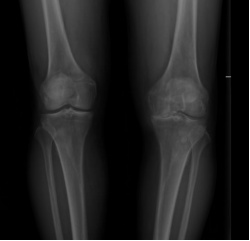

②关节畸形:膝关节因骨赘形成或滑膜炎症积液也可造成关节肿大,膝关节内翻或外翻畸形(即O型腿或X型腿)。

① X线:为膝骨关节炎明确临床诊断的“金标准”,是首选的影像学检查。X线片上的三大典型表现为受累关节非对称性关节间隙变窄、软骨下骨硬化和(或)囊性变、关节边缘骨赘形成。部分患者可有不同程度的关节肿胀,关节内可见游离体,甚至关节变形。